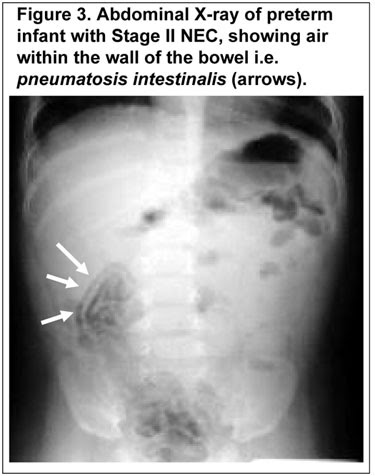

• Necrotising Enterocolitis